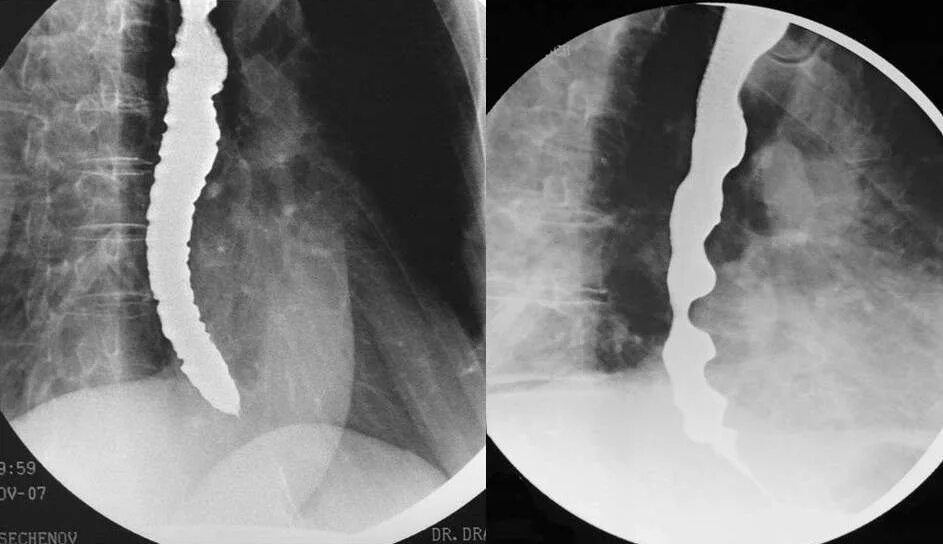

Диффузный эзофагоспазм